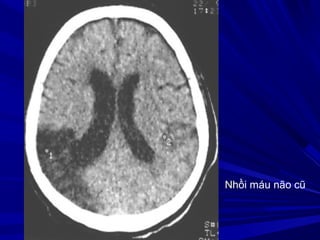

Nhồi máu não cũ

- OÅ ñaämñoä dòch ôû vuøng toån thöông - Teo naõo ( roäng naõo thaát, raõnh naõo ) GIAI ÑOAÏN MAÕN (>8 tuaàn)